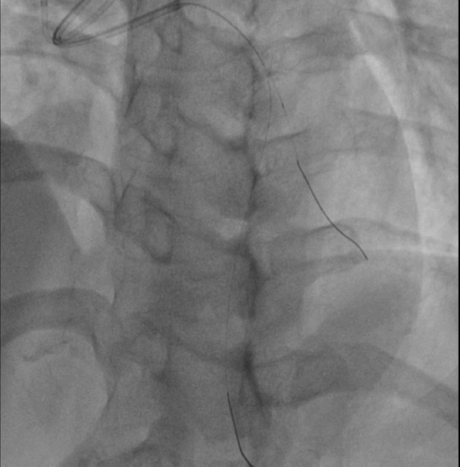

造影

两段闭塞 J-CTO score = 2(blunt tip/bending angle>45°)

无明显钙化,闭塞节段较短,首选对侧造影支持下正向策略

EBU3.0+Finecross微导管+XT-R做初始尝试

必要时升级导丝硬度

注意第二段闭塞成角

操作过程 XT-R顺利通过第一闭塞段

第二段病变通过困难角度过大更换XT-A仍通过失败 交换双腔微导管+Gaia-2

Gaia-2进入内膜下微调进入真腔交换工作导丝进行IVUS检查